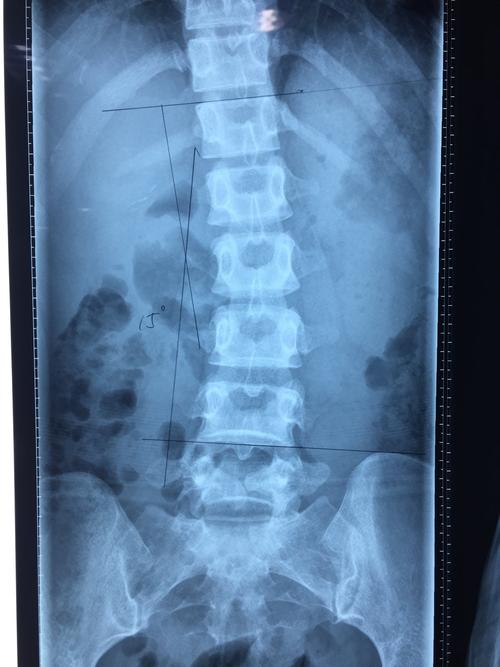

腰椎向右侧弯图片

腰椎向右侧弯图片,腰椎向左侧弯图片

请问这是脊椎向左弯还是向右弯,,这个是腰椎放射x线.

腰椎侧弯图片x光